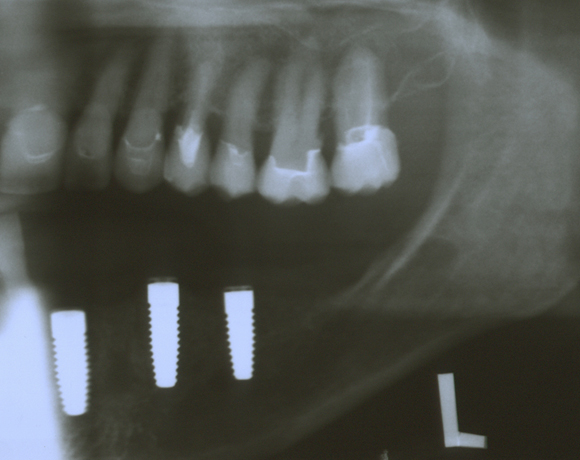

Knochenspaltung Unterkiefer 32 – 36

Die Knochenspaltung auch Bonesplitting genannt, ist eine geeignete Möglichkeit im Unterkieferseitenzahnbereich Knochen aufzubauen, um Implanate setzen zu können. Vorraussetzung ist eine ausreichende Knochenhöhe.